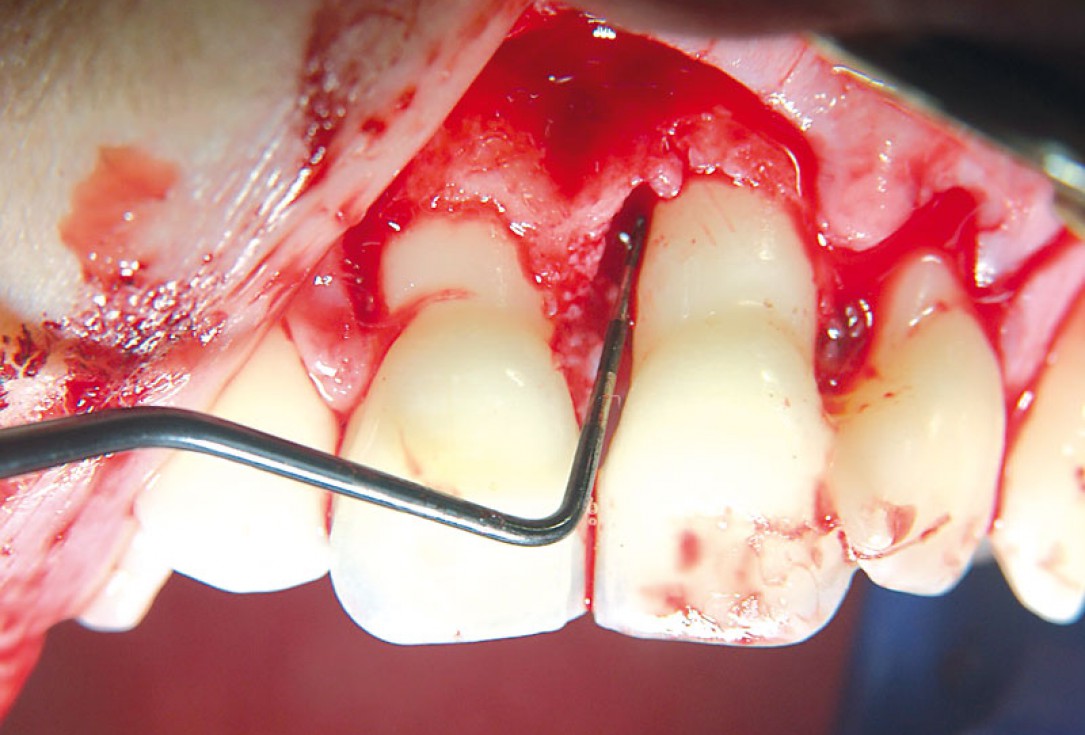

04/11 - Deep intrabony defect on the mesial aspect of tooth 21.Non-contained intrabony defect treated using cerabone®, collprotect® membrane and Straumann® Emdogain® - Dr. T. Schwaar (2)